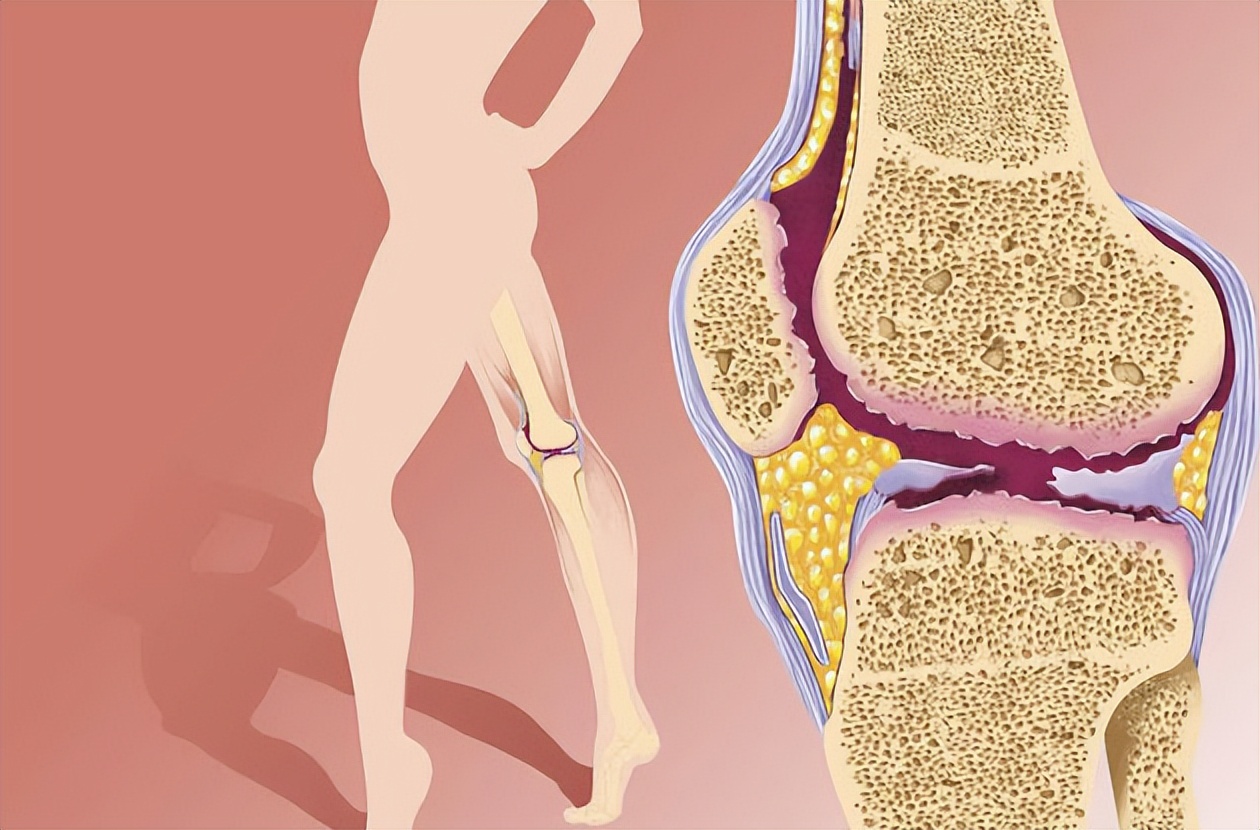

过了50岁,关节健康的保护变得尤为重要,因为随着年龄的增长,关节的磨损和退化风险也增加。

1. 保持适度的体重:过重会增加关节的负担,特别是膝关节。保持适度的体重可以减轻关节的压力,从而降低疼痛和炎症的风险。

2. 均衡饮食:摄入富含维生素C、D和E、钙、镁和锌等关节健康所需的营养物质。这些营养物质有助于维持关节软骨的健康和修复。

8. 补充关节保健品:根据医生建议,可以适量补充一些关节保健品,如葡萄糖胺、软骨素、鱼油等。这些物质有助于维持关节的健康和功能。